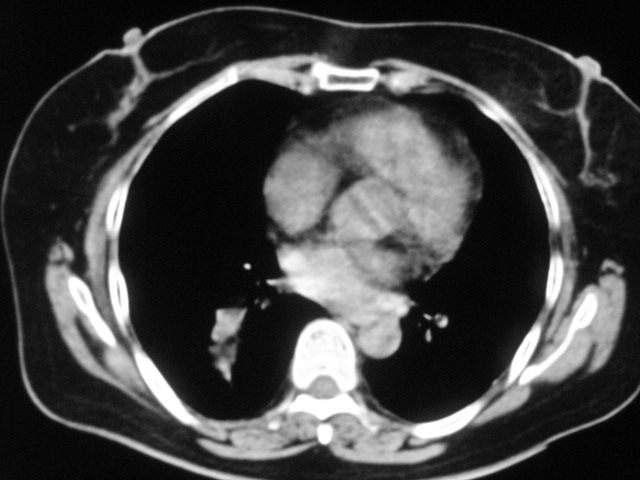

以下是引用清清楚楚在2007-8-28 7:13:00的发言:[br]右肺下叶可见斑片状高密度影,边缘模糊;右肺中叶内侧段及左肺舌段亦可见小斑片状模糊影。[br]考虑双肺感染,建议抗炎治疗后复查。

以下是引用天南地北在2007-8-27 23:49:00的发言:[br]右肺下叶可见斑片状高密度影,边缘模糊;右肺中叶内侧段及左肺舌段亦可见小斑片状模糊影。[br]考虑双肺感染,建议积极抗炎治疗后复查。

以下是引用难听在2007-8-28 13:17:00的发言:[br]右肺下叶背段支气管狭窄,是否可以考虑新生物伴阻塞性肺炎.请大家帮帮忙,这个病人是卫生局长的丈母娘.惹不起啊.